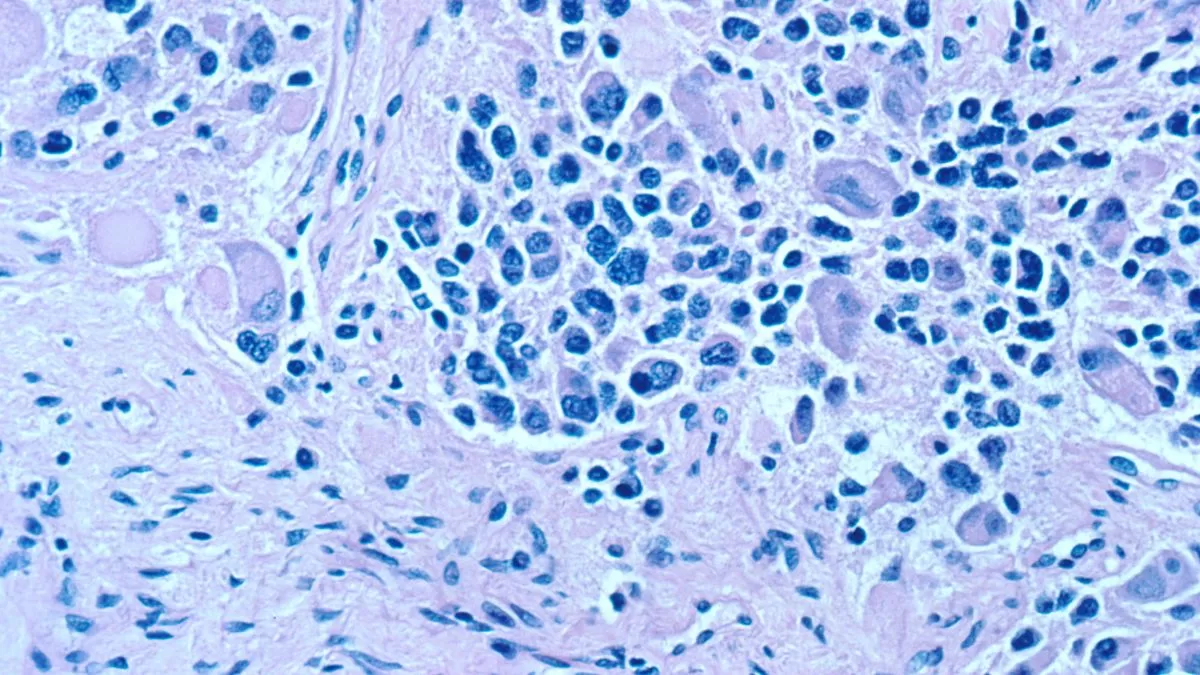

En esta enfermedad, se forman células cancerosas en tejidos nerviosos inmaduros (neuroblastos) y que pueden formarse en el cuello, en las glándulas suprarrenales o incluso en la médula espinal, según detallan en el National Cancer Institute.

Poco después de la inyección, se detectó que la proteína viral NS1 estaba dentro del tumor junto con una gran cantidad de copias virales. Ello condujo a un incremento importante en el tejido necrótico del tumor, al mismo tiempo que una disminución de su masa, según se lee en el estudio.

Así, a partir de la inyección del virus en estos ratones, los tumores formados mostraron inmediatamente una muerte casi completa de los tejidos cancerosos. Además, el experimento arrojó que estos animales de prueba tuvieron una supervivencia prolongada.